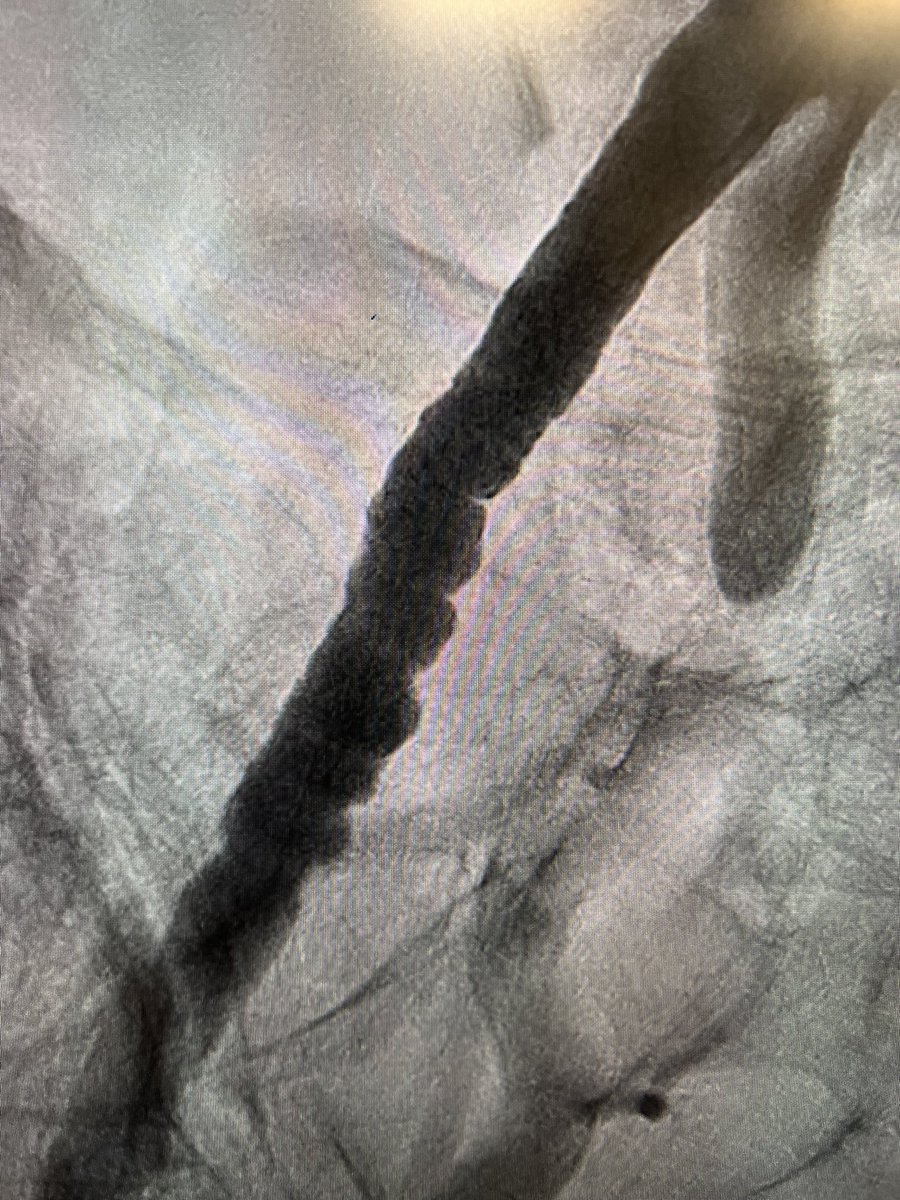

👍 “A Contemporary Algorithm to Guide Percutaneous Coronary Intervention in High-Risk Spontaneous Coronary Artery Dissection” 🤜🤛: 🔗 hmpgloballearningnetwork.com/site/jic/origi……